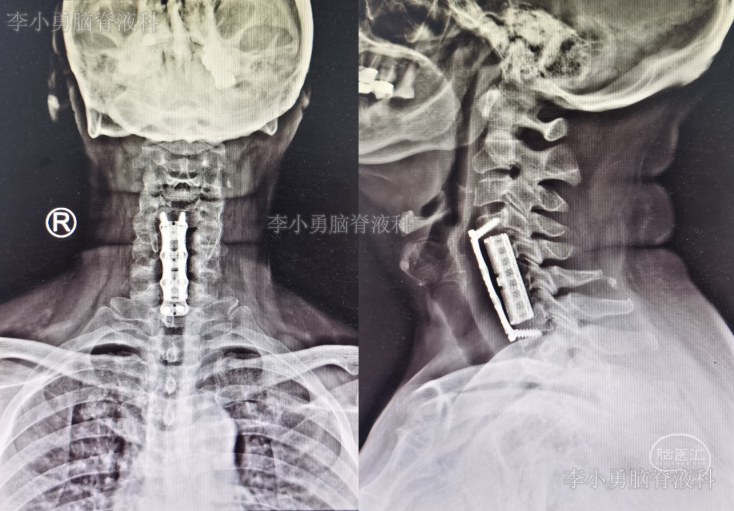

患者因间断性头晕、行走不稳,伴双上肢放射痛,麻木,于2020年4月11日入住北京某三级医院的中医骨伤科,当日查颈椎CT示椎管狭窄性颈椎病(图-1)。

图-1:2020年4月11日颈椎CT

2020年8月4日(即第一次行前路颈5-6椎间盘切除椎间植骨融合内固定术后第114天),再次行颈椎前路颈5、颈6锥体次全切、人工锥体钛板螺钉内固定术,2020年8月5日(即第二次颈椎病术后第1天)复查颈椎平片及颈椎CT示椎管狭窄解除,人工椎体位置良好(图-6、图-7)。

图-6:2020年8月5日颈椎平片